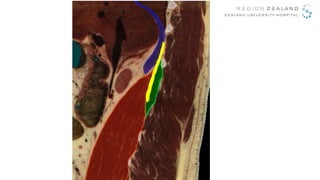

Transverse Oblique Paramedian = TOP TQL block

Anterior

Posterior

L4

• WHEN: Indicated for abdominal and

retroperitoneal surgery

• WHERE: Administered between QL and PMM

• WHY: Spreads to the Thoracic Paravertebral Space

• WHY: Alleviates visceral pain

• WHY: Long lasting effect > 24 hours

• HOW: It’s obvious – the TEQUILA way!